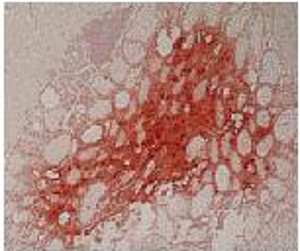

Kl. Pathologie und Genetik neuroendokriner Tumore | Fallberichte | Klinische Studien |